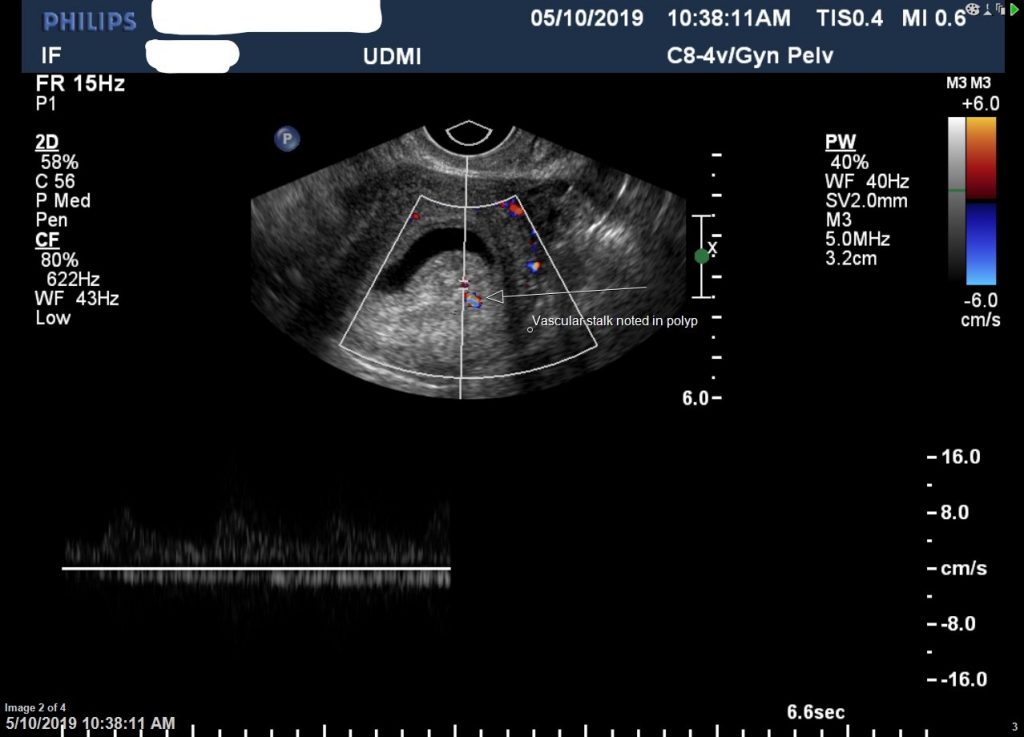

Hysterosonogram Med Image Diagnostic Centre Fertility Test Hysterosonogram The hsn provides the best imaging of the contour of the uterine cavity. All couples concerned about fertility should be offered an initial assessment (history and examination) in primary care to identify those. Salpingo = fallopian tube) involves viewing the uterus, fallopian tube and the other organs that. At markham fertility centre (mfc) we offer many testing options, one of. Fertility Test Hysterosonogram.

HSN / Hysterosonogram IVF1 Fertility Fertility Test Hysterosonogram The purpose is to detect any abnormalities. Tests to find out the cause of infertility in women include: At markham fertility centre (mfc) we offer many testing options, one of which is a sonohysterogram (shg), also known as a saline infusion sonogram (sis) or. The hsn provides the best imaging of the contour of the uterine cavity. It is an. Fertility Test Hysterosonogram.